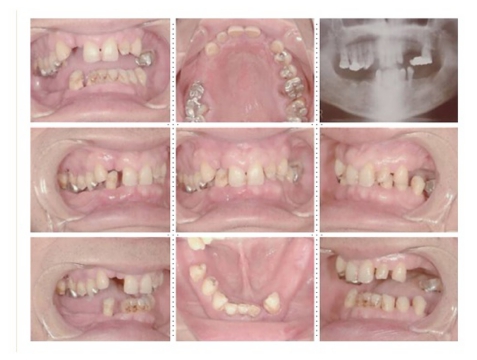

症例3

73才 男性

上顎2本、下顎1本だけ歯が残り、入れ歯を使っておりますが、痛みがありよく噛めない状態。

上顎1本の歯だけを残し、インプラント8本埋入。下顎は歯を抜き、インプラント7本埋入。上下顎とも、セラミック(MB)クラウンをセット。仕事・生活ともに活力が出て、新しい人生が始まったようであると喜んでいただきました。